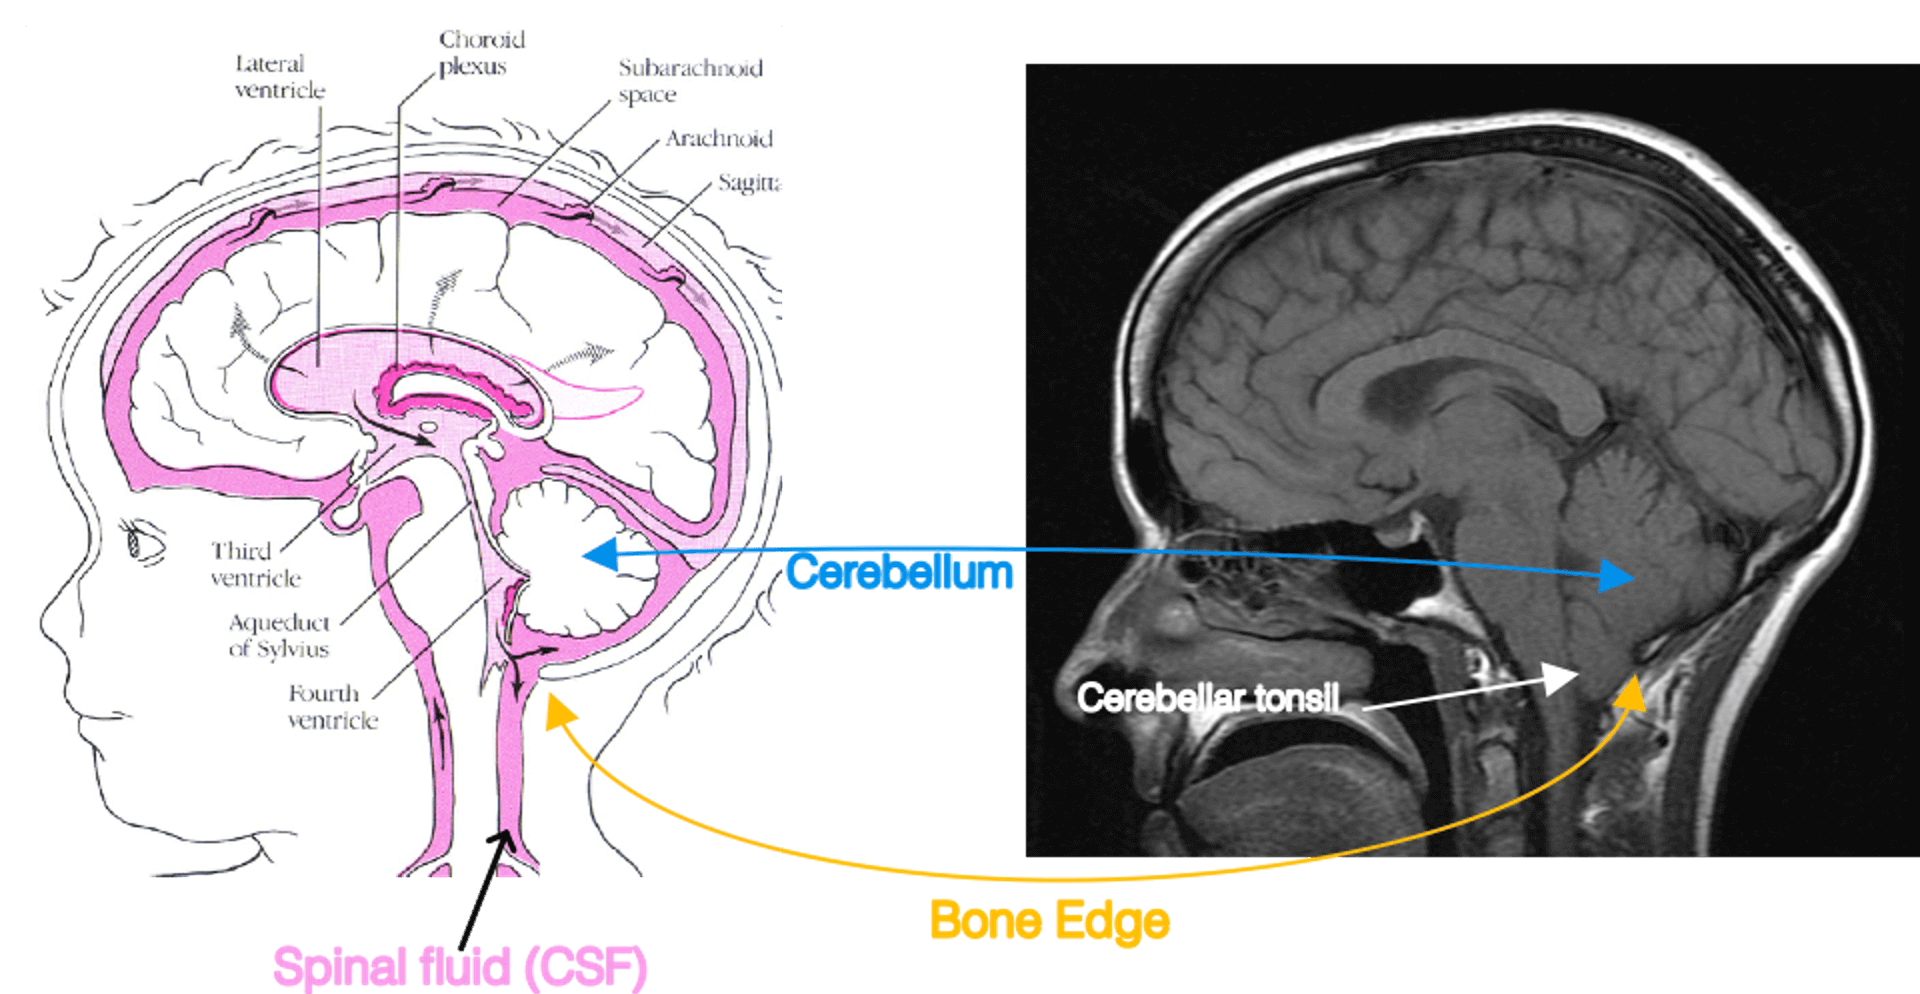

As a morphological disease condition, Chiari I is rooted in a disproportionality of the volume of the post fossa compared to the contained brain structure. These brain structures include the brainstem and the cerebellum. The cerebellum is a brain structure within the lower back part of the head as illustrated on the left side of Fig. 1. This compartment in the lower back part of the head is called the post fossa. There is a hole through the bone in the bottom of the post fossa called the foramen magnum. This is the passageway through which the brainstem exits and becomes the spinal cord within the spinal canal. In the standard anatomical configuration as on the left side of Fig. 1, the cerebellum and the brainstem are bathed in spinal fluid in the vicinity of the foramen magnum.

Fig. 1. The cerebellum and its compression in Chiari I. Left: A diagram adapted from the Hydrocephalus Association. Right: A teaching file mid-sagittal MRI of Chiari I. In Chiari I, the cerebellum is compressed by abnormal bone formation. This causes the cerebellar tonsil to extrude into the spinal canal.In Chiari I malformation, the post fossa compartment is comparatively too small for the brain tissue volume occupied by the cerebellum and brainstem. Some of these findings are shown on the right side of Fig. 1, which is a midline sagittal T1 image of a symptomatic Chiari patient adapted from a human brain MRI teaching file. As a consequence of the comparatively small post fossa case volume compared to the brainstem and cerebellum, the bottom part of the cerebellum (called the cerebellar tonsils) and the brainstem are crowded in the foramen magnum. There is reduced or even absent spinal fluid bathing them at the foramen magnum. The cerebellar tonsils may exit out of the skull cavity and into the top posterior part of the spinal canal.